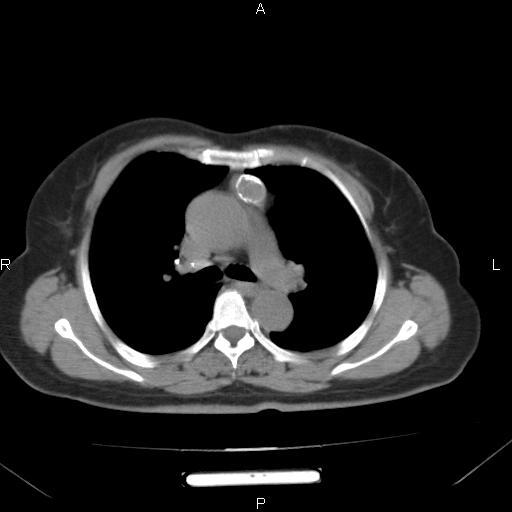

胸腺瘤

女、63Y 双眼睑下垂,早轻晚重。 胸腺瘤???

结果胸腺瘤